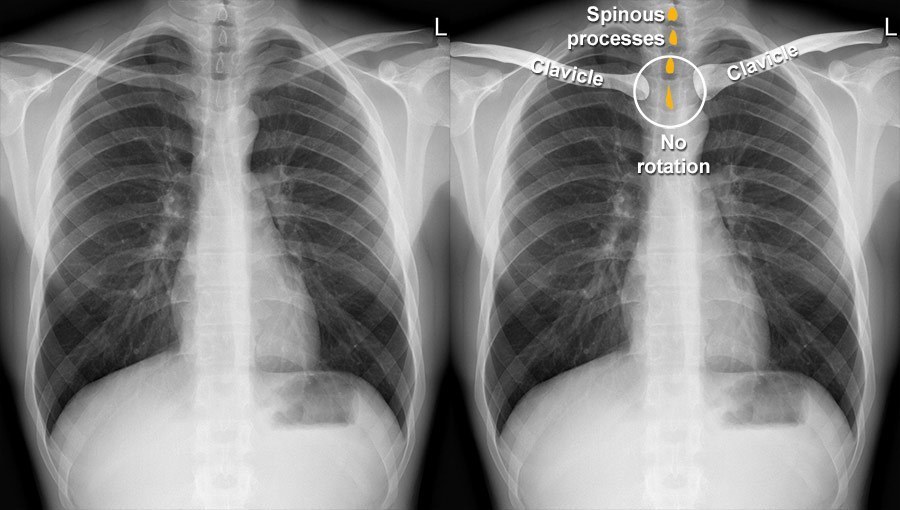

Деректер жинау – ашық интернет дерекқорларынан «сау өкпе» және «ауру өкпе» суреттерін таңдау;

Сау өкпе

Пневмониялы өкпе